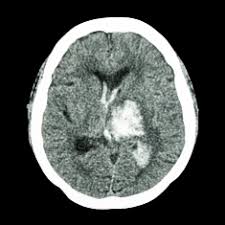

Aceste efecte se datorează proprietăților antiinflamatoare, cicatrizante, antiseptice și sedative ale tămâii. Acest cheag este situat în venă între creier şi craniu, în spatele urechii drepte, a declarat doctorul lisa bardack.

Simptomele sunt urmatoarele cheagurile de sange la nivelul creierului pot cauza probleme cu vederea.

Cheagurile de sange care sunt simptomele si factorii de risc farmacia ta farmacia ta. A murit în timpul antrenamentului! In plus, puteti experimenta dificultatea in vorbire si dureri de cap ingrozitoare.

Închegarea sângelui este un proces necesar supraviețuirii un cheag de sânge format la nivelul plămânului se numește embolism pulmonar și este una dintre cele mai periculoase afecțiuni medicale. Secretarul de stat american, hillary clinton, internată în spital duminicã pentru a i se trata un cheag de sânge la nivelul capului, a părăsit miercuri spitalul prezbiterian din. Cheagul de sange sau trombusul este produsul final al coagularii sangelui din procesul de hemostaza.

Tromboza se manifesta prin formarea unui cheag de sange si migrarea acestuia catre un organ vital. Când se formează fără a fi nevoie, duce la atac de cord, chiar deces. Cheagurile de sange care sunt simptomele si factorii de risc farmacia ta farmacia ta.